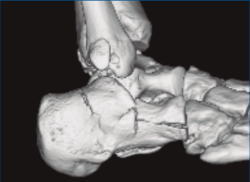

Figura 3. Desplazamiento entre fragmento anteromedial (sustentaculum tali) y posterolateral (tuberosidad).

Se trata de un varón de 19 años que ingresa en reanimación tras precipitarse desde una altura de aproximadamente 10 metros. El paciente presenta una fractura estallido de L3 con afectación del canal medular junto con una fractura del vértice inferior de L4, así como una fractura luxación de calcáneo, asociada a una fractura del maléolo peroneo y del maléolo tibial posterior (Figuras 1 a 6) diagnosticadas mediante TC total body (por eso no se dispone de radiografías simples al momento del ingreso). Como podemos comprobar, se trata de una fractura de doble trazo de tipo hundimiento/depresión de la carilla articular (Figuras 5 y 6).

Figura 4. Luxación fragmento posterolateral.

Figura 5. Fractura maléolo peroneo, luxación astrágalo, fractura de doble trazo en calcáneo.

Figura 6. Fractura de doble trazo; se evidencia afectación de la articulación calcaneocuboidea.